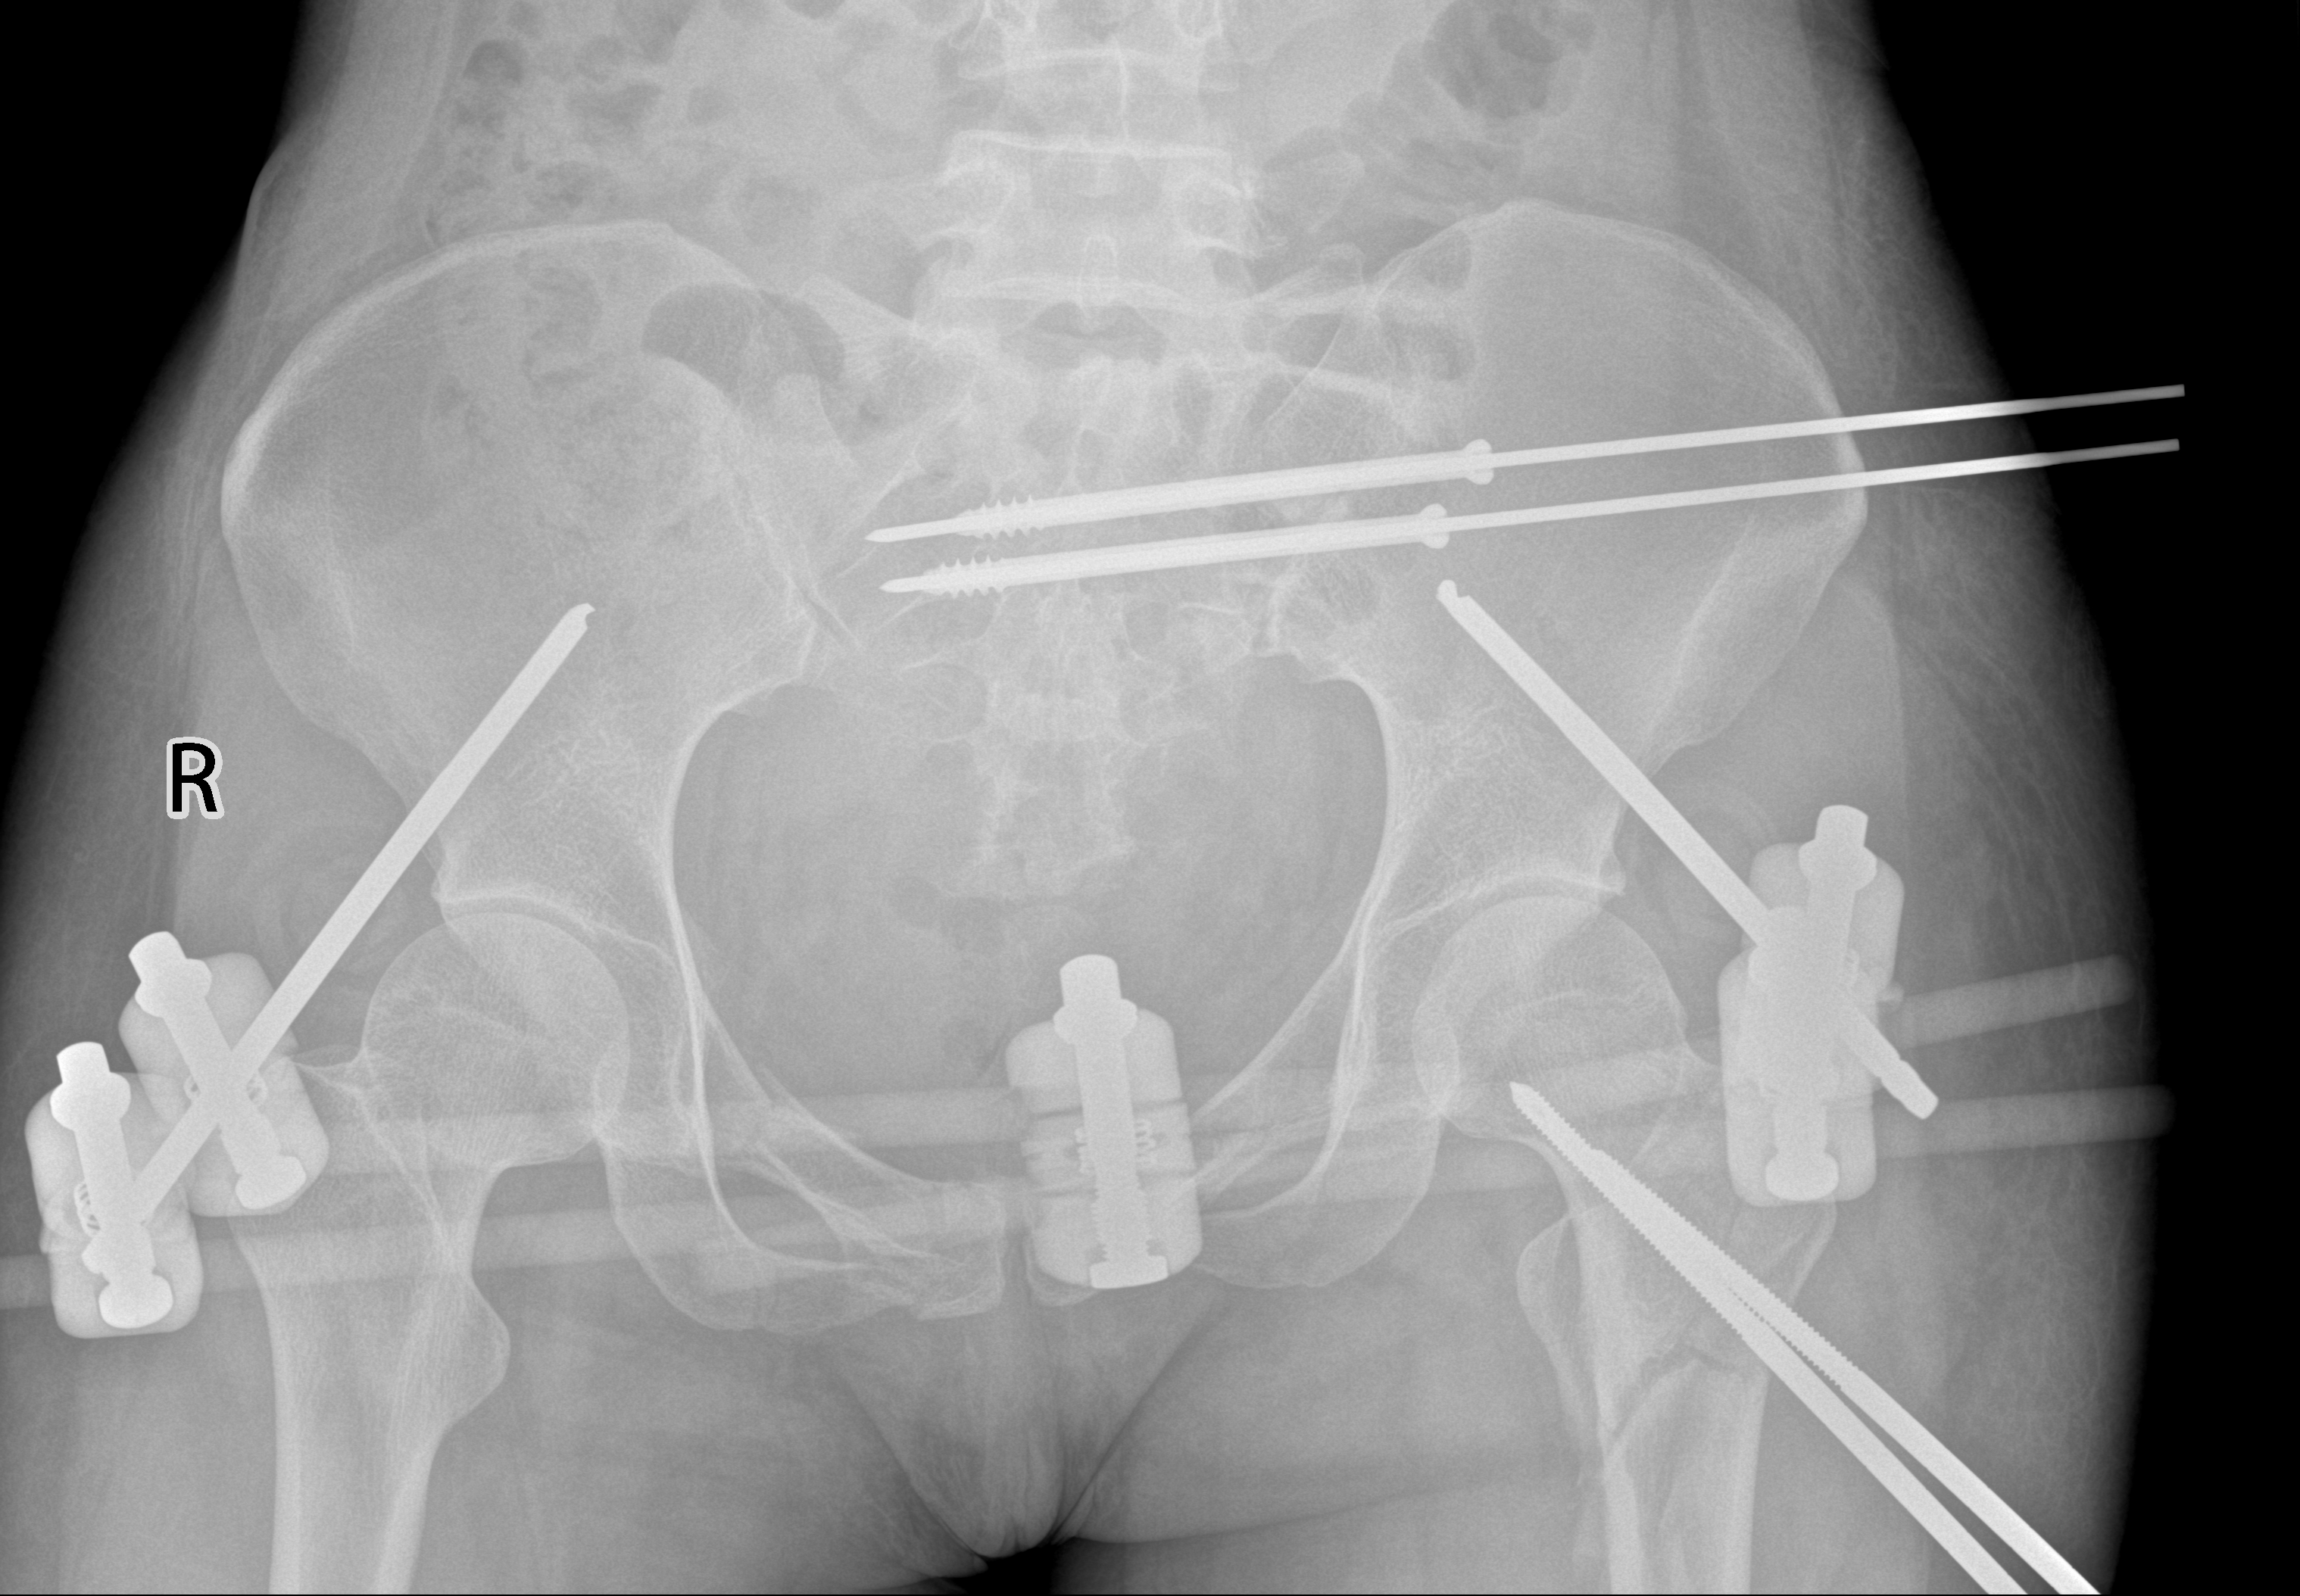

术后

又是一天的凌晨,一名23岁的年轻男性骑摩托车发生严重车祸,同样为严重骨盆骨折,通过迅速启动创伤救治绿色通道,很快为患者紧急进行了急诊骨盆外固定架临时固定手术,挽救了患者生命,为二期手术赢得了宝贵的时间。

术前